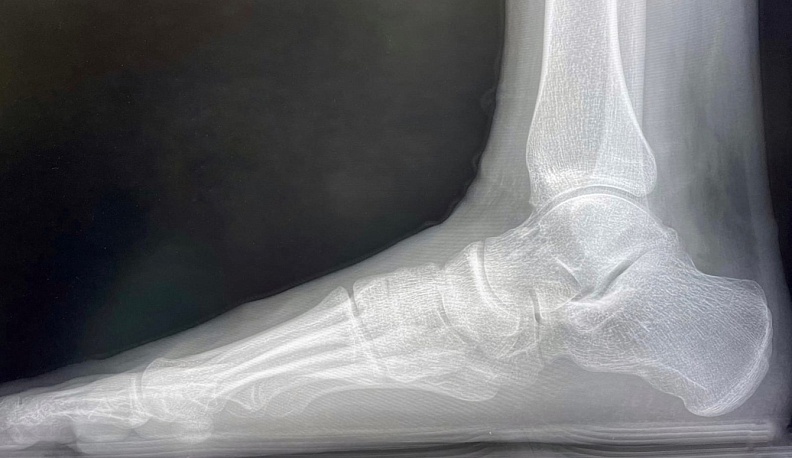

«Основная нагрузка пришлась на Центр травматологии и ортопедии. 189 пациентов принято в травмпункте, 24 из них госпитализировано, проведено 11 операций в стационаре. Частая причина обращений — «уличные» травмы»,